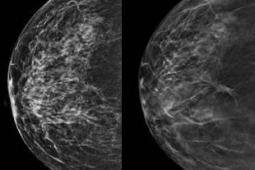

Mammografia trójwymiarowa piersi wykrywa więcej nowotworów

Mammografia trójwymiarowa wykorzystująca zaawansowane techniki obrazowania piersi, określana mianem cyfrowej tomosyntezy piersi, wykrywa znacznie więcej nowotworów piersi niż standardowa mammografia cyfrowa i może potencjalnie zmniejszyć dawkę promieniowania oraz obciążenie związane z badaniami przesiewowymi w kierunku raka piersi - mówią szwedzcy badacze.